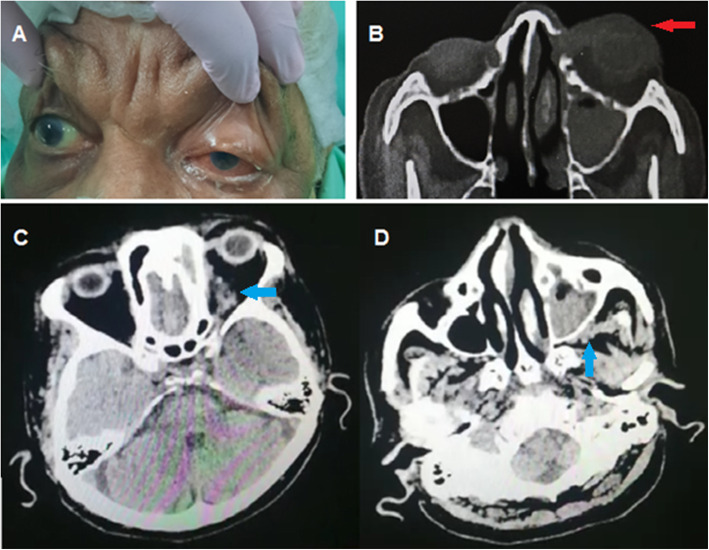

The patient presented with 6 days duration of right total ophthalmoplegia, ptosis, conjunctival chemosis, and proptosis (Fig. 5) and blackish discoloration of hard palate.

Fig. 5.

Chemosis of conjunctiva and total ophthalmoplegia with ptosis elevated by the examiner’s finger

CT paranasal sinuses revealed pan sinusitis along the right maxillary, ethmoidal, and frontal sinuses with obliteration of the ostiomeatal complex.

MRV cavernous view with contrast showed enhancement and filling defect.

A provisional diagnosis of rhino-cerebral-mucormycosis and associated cavernous sinus thrombosis was considered, and the patient underwent complete drainage of the sinuses; the culture revealed growth of zygomycetes fungi as well as Klebsiella multiple-drug resistant (MDR).